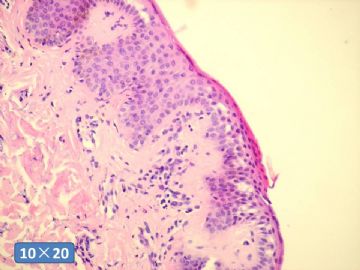

背部皮损。

MALE

62

skin of back,

scaly and red spots on arms and back, symptomless.